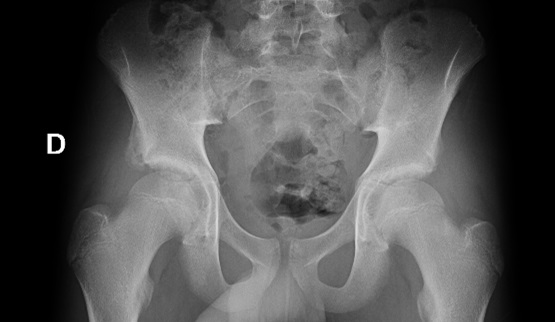

Varón de 14 años de edad que presenta de manera súbita dolor en región inguinal derecha e impotencia funcional de pierna derecha tras dar una patada al balón mientras jugaba al fútbol. En la exploración presenta dolor a la palpación en región inguinal derecha y a la movilización pasiva, principalmente para la flexión de la cadera. Sin hematomas, impotencia funcional en miembro inferior derecho, consigue bipedestación con imposibilidad para deambular. Se realiza una radiografía simple anteroposterior de pelvis, en la que se evidencia una fractura por avulsión de la espina ilíaca anteroinferior derecha (Figura 1). Ante los hallazgos radiográficos se indica tratamiento conservador, reposo relativo con carga parcial de la extremidad con ayuda de dos muletas durante 2-3 semanas.

Figura 1. Radiografía simple anteroposterior de pelvis